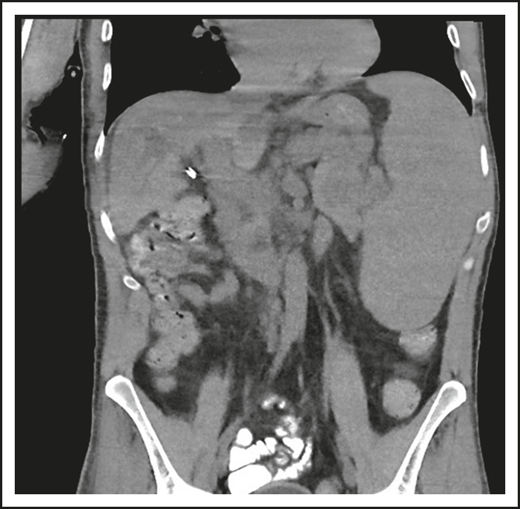

A third common reason for hematologists to see patients with CVID is a suspicion of lymphoma. Patient 3 is now a 47-year-old computer executive who came for a second opinion to the immunology department. He had had numerous sinopulmonary infections in childhood and then 2 episodes of shingles in his 30s. At the age of 36, he had acute AIHA treated with steroids. He then had an episode of cellulitis, and, with this, serum immunoglobulins were tested, which showed quite low levels: IgG, 186 mg/dL; IgA, 9 mg/dL; and IgM, 24 mg/dL. At the same time, his spleen was quite large. He was diagnosed with CVID, and immunoglobulin therapy was initiated. Owing to the enlarged spleen, now at 19 cm, a bone marrow biopsy was performed, and he was ultimately seen at another center at the age of 42, when the diagnosis of marginal zone lymphoma was made on the basis of bone marrow findings. He was treated with 6 cycles of rituximab and bendamustine. However, his splenomegaly persisted, and 3 years later, he sought an opinion at another medical center, where he was told that he did not have lymphoma on the basis of National Cancer Institute review of his bone marrow. Now, 5 years later, he has been well while receiving intravenous immunoglobulin, but he continues to have an enlarged spleen. There are no signs of lymphoma (Figure 3).

The patient in clinical case 3 was concerned because after he received chemotherapy for a presumed lymphoma, his spleen remained large. However, this is typical in patients with CVID.